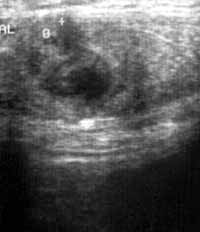

Абсцесс передней брюшной стенки.

Рис. 1. Передняя брюшная стенка при продольном сканировании. Лоцируется участок пониженной эхогенности 11 мм в диаметре.